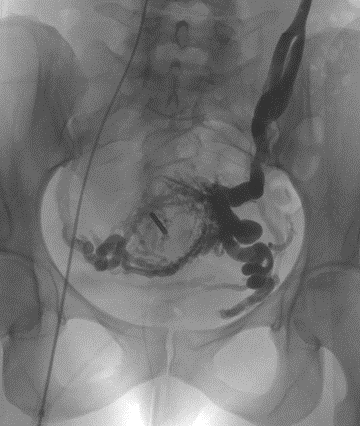

- Phlébographie de la veine ovarienne gauche mettant en évidence les volumineuses varices pelviennes

Les varices pelviennes ont le plus souvent pour origine un reflux anormal dans la veine ovarienne gauche ou les veines iliaques internes.

- Un premier temps diagnostique : la Phlébographie.

Par ponction d’une veine du bras ou de l’aine, le radiologue va réaliser un bilan vasculaire des varices grâce à un cathéter et une injection de produit de contraste sous contrôle radiographique. - Un deuxième temps thérapeutique : l’Embolisation